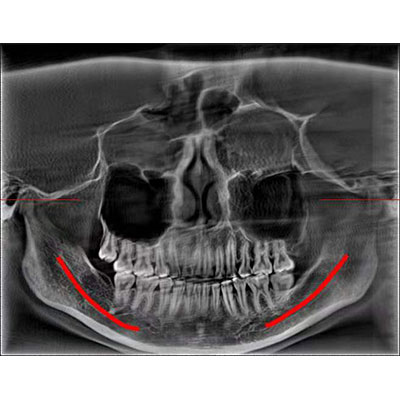

高清口腔三維CT/全景影像 PLX3000A

通過(guò)三維容積影像,提取高清口腔全景影像。